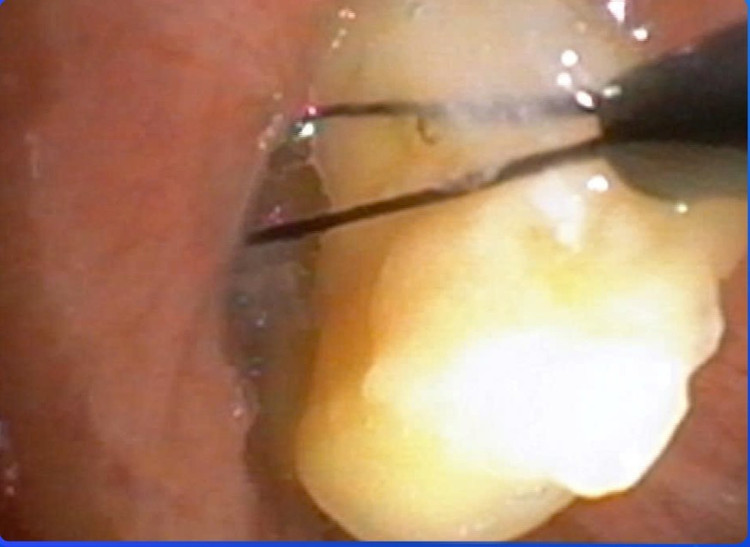

hat-ngo-2.jpg

Nội soi lấy hạt ngô gây tắc đường thở cho bệnh nhân - Ảnh BVCC

Người bệnh được chuyển thẳng vào Đơn vị Nội Soi, tiến hành nội soi phế quản ống mềm cấp cứu dưới gây mê. Qua nội soi, các bác sĩ phát hiện nhiều hạt bắp mắc kẹt trong phế quản, gây bít tắc đường thở và là nguyên nhân trực tiếp dẫn đến suy hô hấp. Bằng các dụng cụ chuyên dụng, ê-kíp đã gắp thành công dị vật, giải phóng đường thở cho người bệnh.